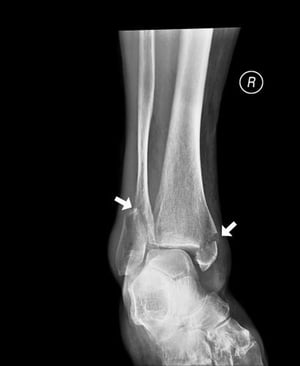

경골축의 횡방향 골절

이 횡방향 골절은 경골의 중축에 영향을 미칩니다.

이미지 제공: Danielle Campagne, MD.